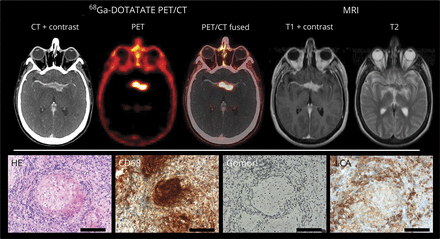

一个45岁的男人面对增加视力损害。MRI显示非特异性在海绵窦病变;一个额外的68年Ga-DOTATATE PET / CT显示这是一个相当高的68年Ga-DOTATATE吸收病变(图)。脑立体定向活检和执行显示神经的最初表现。68年Ga-DOTATATE目标生长激素抑制素受体(SSR),这是表达的肿瘤细胞在神经内分泌肿瘤等恶性肿瘤和脑膜瘤,但也通过激活巨噬细胞,1在神经。目标是使用SSR标记配体与β放射同位素的放射性核素治疗患者可能提供额外的治疗选项难以neurosarcodosis,2也有效地应用于SSR-positive恶性肿瘤。

MRI:充当在海绵窦病变病灶周边水肿和接触交叉和血管。68年Ga-DOTATATE PET / CT:高68年Ga-DOTATATE吸收。苏木精和伊红染色:noncaseating上皮样肉芽肿。CD68染色:紧密epitheloid巨噬细胞。Gomori染色:初期perigranulomatous纤维化包围白细胞共同抗原(LCA)阳性淋巴细胞(放大×20、酒吧100μm)。